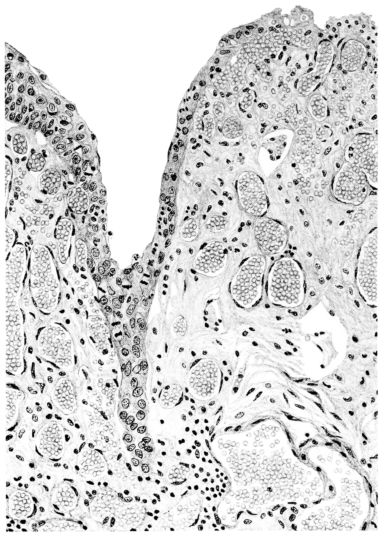

FIG. III. AUTOPSY NO. 90. DRAWING FROM A LESION OF THE TRACHEA (SOMEWHAT OLDER THAN THAT ILLUSTRATED IN FIGURE II). THE MUCOSA IS ENTIRELY LACKING. CONGESTION AND EDEMA ARE THE STRIKING FEATURES IN THE SUBMUCOSA. THE NECROTIZING PROCESS HAS EXTENDED INTO THE MUCUS GLANDS. THIS IS SHOWN IN THE LOWER PICTURE.

The changes are less marked, perhaps, in the trachea than in its finer ramifications. The mucosa is constantly more or less destroyed and large areas, usually focal, are entirely devoid of their epithelial covering. This is replaced by a sparse exudate, composed largely of red blood cells, mucus, a small amount of fibrin, and nuclear fragments (Fig. II). It may dip into the submucosa for a short distance, but usually these indentures are associated with the ducts of the mucous glands into which the inflammatory reaction extends. A more striking feature than the exudate, however, is the edema and the congestion of the submucosa. The loose areolar tissue of the submucosa is spread widely apart, and throughout it distended blood vessels are very conspicuous. Occasionally such a vessel is broken and actual hemorrhage appears in the submucosa. Occasionally, too, the inflammation extends down the duct to the mucous gland itself, and here, also, aplastic inflammatory reaction is evident, inasmuch as the acini now stain intensely red with the cells undifferentiated from each other and specked here and there by broken remains of the dead nuclei (Fig. III). After the disease has continued for a short period, even at the end of five or six days, some regeneration of the epithelial lining may be seen (3) (Fig. IV). But despite this, the acute picture persists, and there goes on, side by side, an attempted repair characterized by epithelial regeneration and the same evidence of acute change. Since the lesion is essentially a superficial one, scars or contractures of any extent are not encountered in the trachea, even in examples of the disease that have ended fatally only after many weeks.[4]